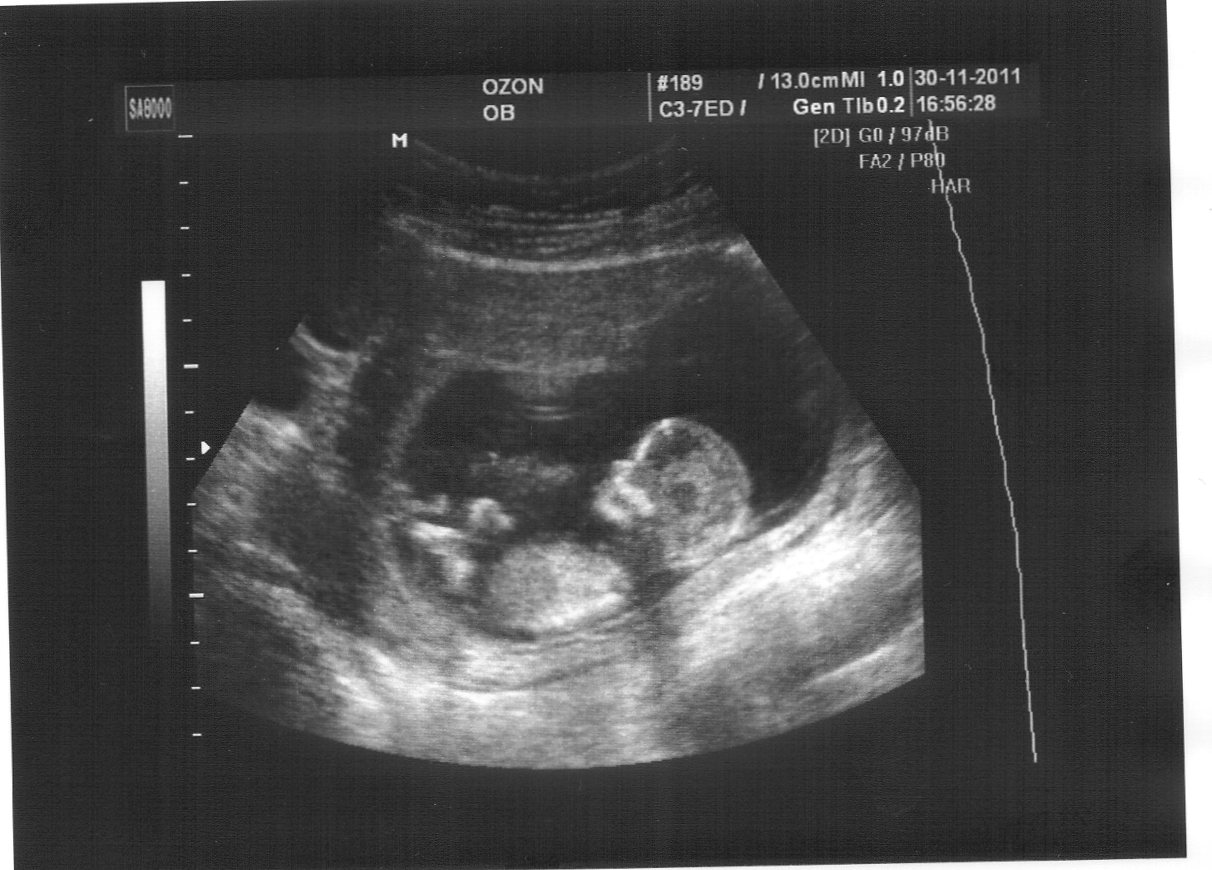

CVmb70xVXn8XMnN: «Игорь, привет! Расскажу тебе свою историю. Я могу точно сказать о том, что ты подобного не переживал в своей жизни. История наша увидела свой свет в городе Томске. Мы ждем дочу... Нашу долгожданную дочу. Это наш первый ребёнок. И тут... Патология... В итоге наша доча родилась в новом перинатальном центре на 7-м месяце весом 1,03 кг. У нее был порок сердца, кровоизлияния в оба полушария. Врачи говорили: ничего не ждите от ребенка, он обречен... Но мы, не сдаваясь, делали для своего дитя всё! Читали ей в кувезе сказки, учили музыке... Верили, что все будет хорошо. Врачи шли с нами до конца. И не поверишь, Игорян! Она растет и радует нас! Идет в этом году в школу. Ты представь, что твоя дочь родилась без рук. Ты бы от нее отказался? Если это так, то ты слабак. Ты нищий духом. И ты политик? Мне стыдно за тебя. Опомнись и возьми свои слова обратно!»